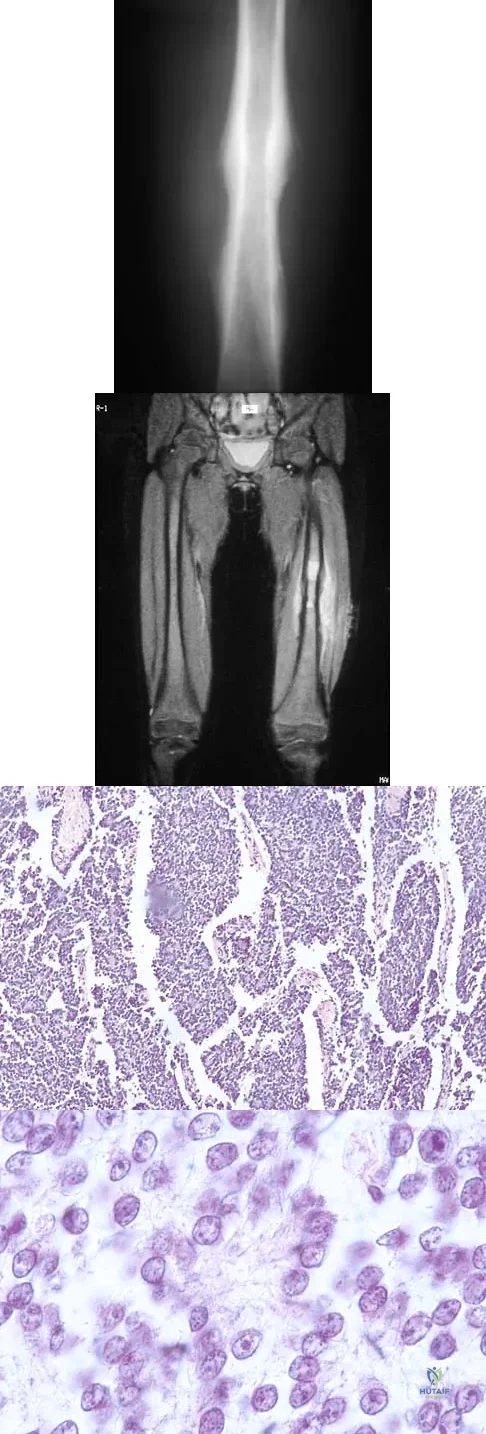

A 13-year-old girl has had right groin pain for the past 3 weeks. She denies any history of trauma. Examination of the hip reveals no palpable soft-tissue mass or lymphadenopathy, and there is full range of motion. A plain radiograph and MRI scan are shown in Figures 15a and 15b. Biopsy specimens are shown in Figures 15c and 15d. What is the most likely diagnosis?

Options:

- Fibrous dysplasia

- Osteosarcoma

- Ewing's sarcoma

- Periosteal chondroma

- Aneurysmal bone cyst

Correct Answer: Fibrous dysplasia

Explanation:

Fibrous dysplasia frequently occurs in the proximal femur. Microfractures and remodeling can lead to the classic "Shepherd's crook deformity." The lesion has a ground-glass appearance on plain radiographs. The histologic appearance shows proliferating fibroblasts in a loose spindle cell background. Dysplastic metaplastic trabeculae are arranged in an irregular or "Chinese letter" appearance. Enneking WF, Gearen PF: Fibrous dysplasia of the femoral neck: Treatment by cortical bone grafting. J Bone Joint Surg Am 1986;68:1415-1422.